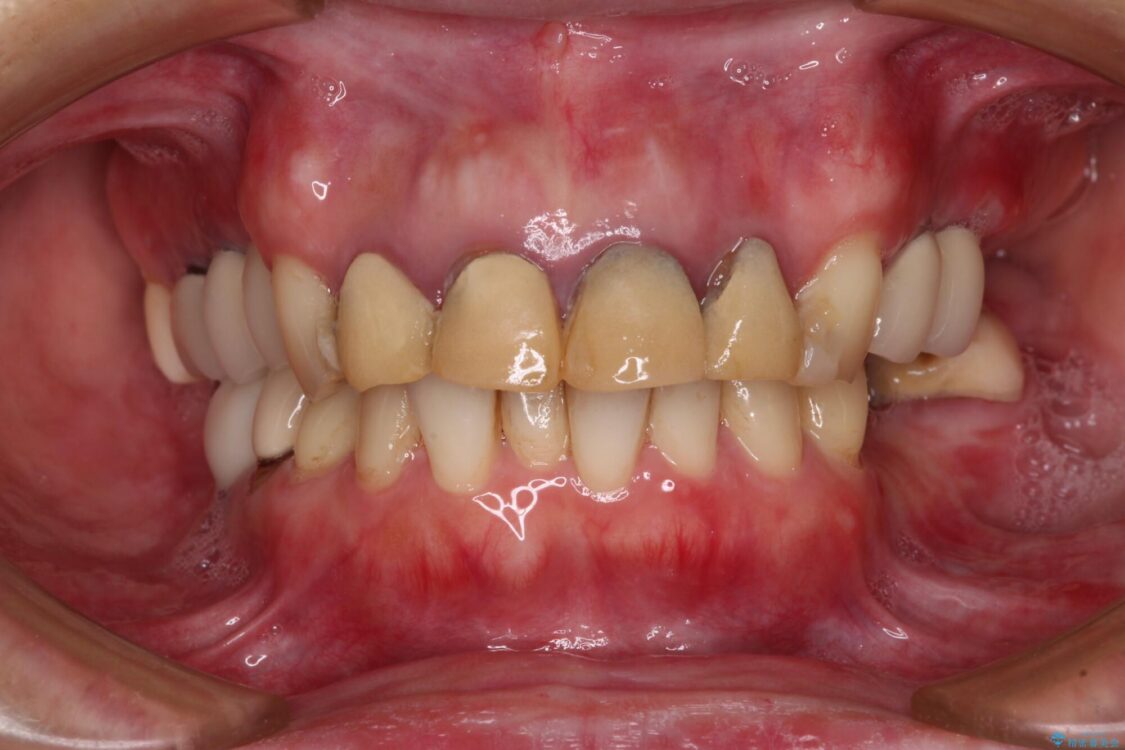

治療前

• 仮歯のまま放置した前歯 オールセラミッククラウンで自然な前歯に 治療前画像

仮歯装着後に放置してしまい、恥ずかしいとのことで来院された患者様です。

治療計画

仮歯が不適合で歯肉が腫脹していたため、しっかりと調整した新しい仮歯にして腫れを改善した上で、オールセラミッククラウンにて補綴することとしました。